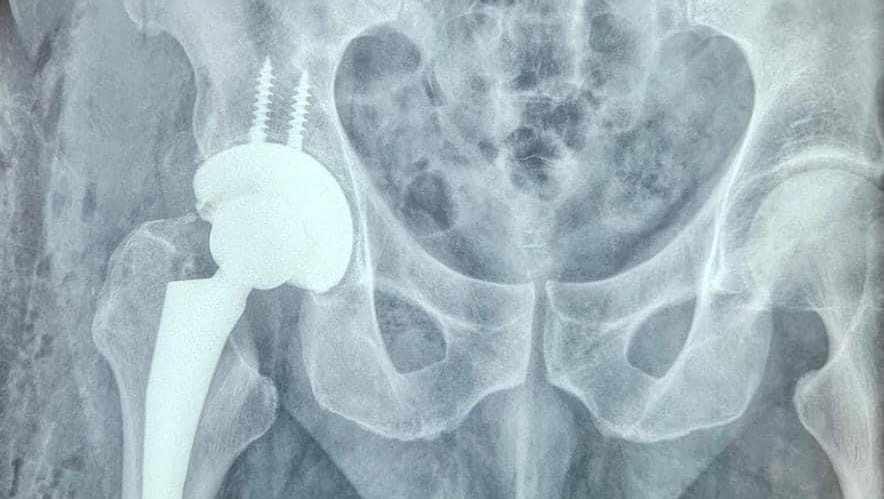

Hello. Finally a hip revision surgery date is set, February 12. Thank you for the donations that poured in, in December. They were a great help for all of the cash expenses I incurred going through the medical process in Costa Rica. This month the process began again in Texas with a new deductible and out of pocket maximums.

I just counted, I attended 16 medical appointments since January 1st here in Dallas. They have had real difficulty determining why the hip replacement failed. Hence a barrage of tests, imagings, scans and consults were done. I am now diagnosed and scheduled for revision surgery.